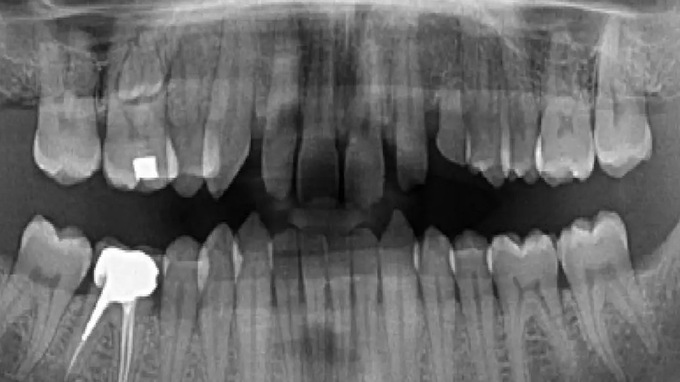

IMAGERIE 2D

- La radiographie panoramique en 2023 : un outil indispensable ?

- Les capteurs numériques intra-buccaux : principes de fonctionnement et protocole d'utilisation des différents capteurs.

- Nombreux cas cliniques :implantologie, parodontologie,chirurgie buccale, endodontie,orthodontie, ...